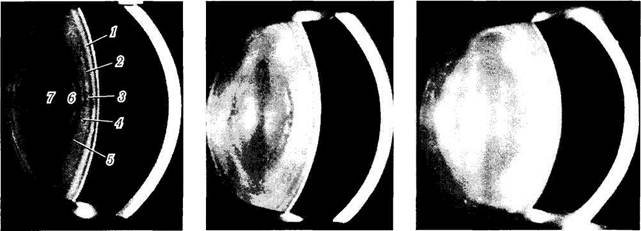

а 6 6

Рис. 3.4.3. Послойность строения хрусталика при биомикроскопическом его исследовании у индивидуумов различного возраста (по Bron et al., 1998):

а — возраст 20 лет; б — возраст 50 лет; s — возраст 80 лет (/ — капсула; 2 — первая кортикальная светлая зона (С1 альфа); 3 — первая зона разобщения (С1 бета); 4 — вторая кортикальная светлая зона (С2): 5 — рассеивающая свет зона глубокой коры (СЗ); 6 — светлая зона глубокой коры; 7 — ядро хрусталика. Отмечается увеличение хрусталика и усиление рассеивания света